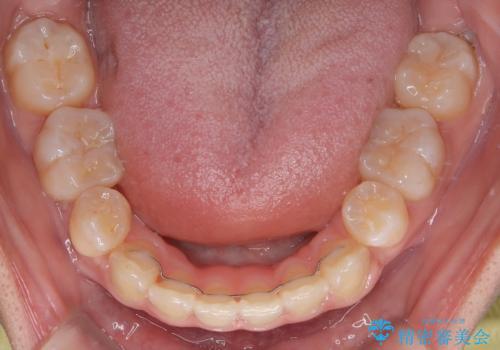

舌のトレーニングは継続して行ってもらっているため、開咬や抜歯したスペースの後戻りはなく、経過は良好です。